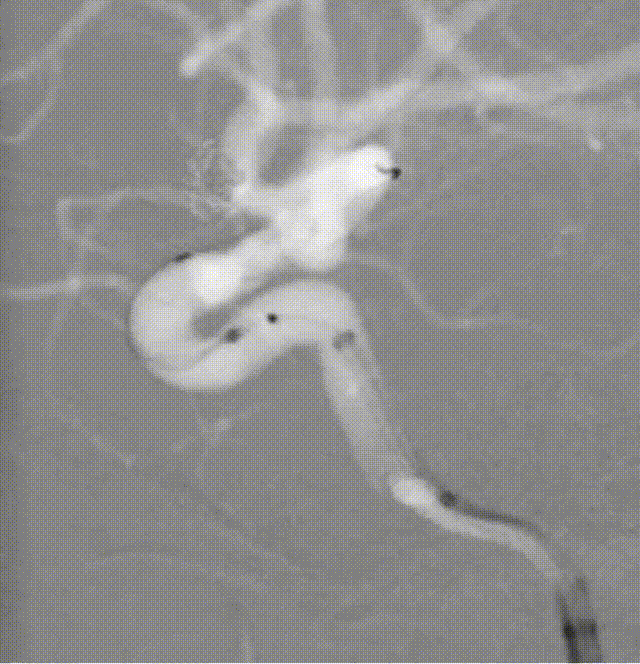

术前诊断:RICA不规则动脉瘤

手术方案拟定:经股行RICA不规则动脉瘤血流导向装置植入术

4、缓慢推挤释放4.5mm×25mm TB:造影确认TB远端位置,逐步推挤释放,直至完全释放TB

5、术后即刻影像:稀释造影及重建,TB贴壁良好,血流通畅。